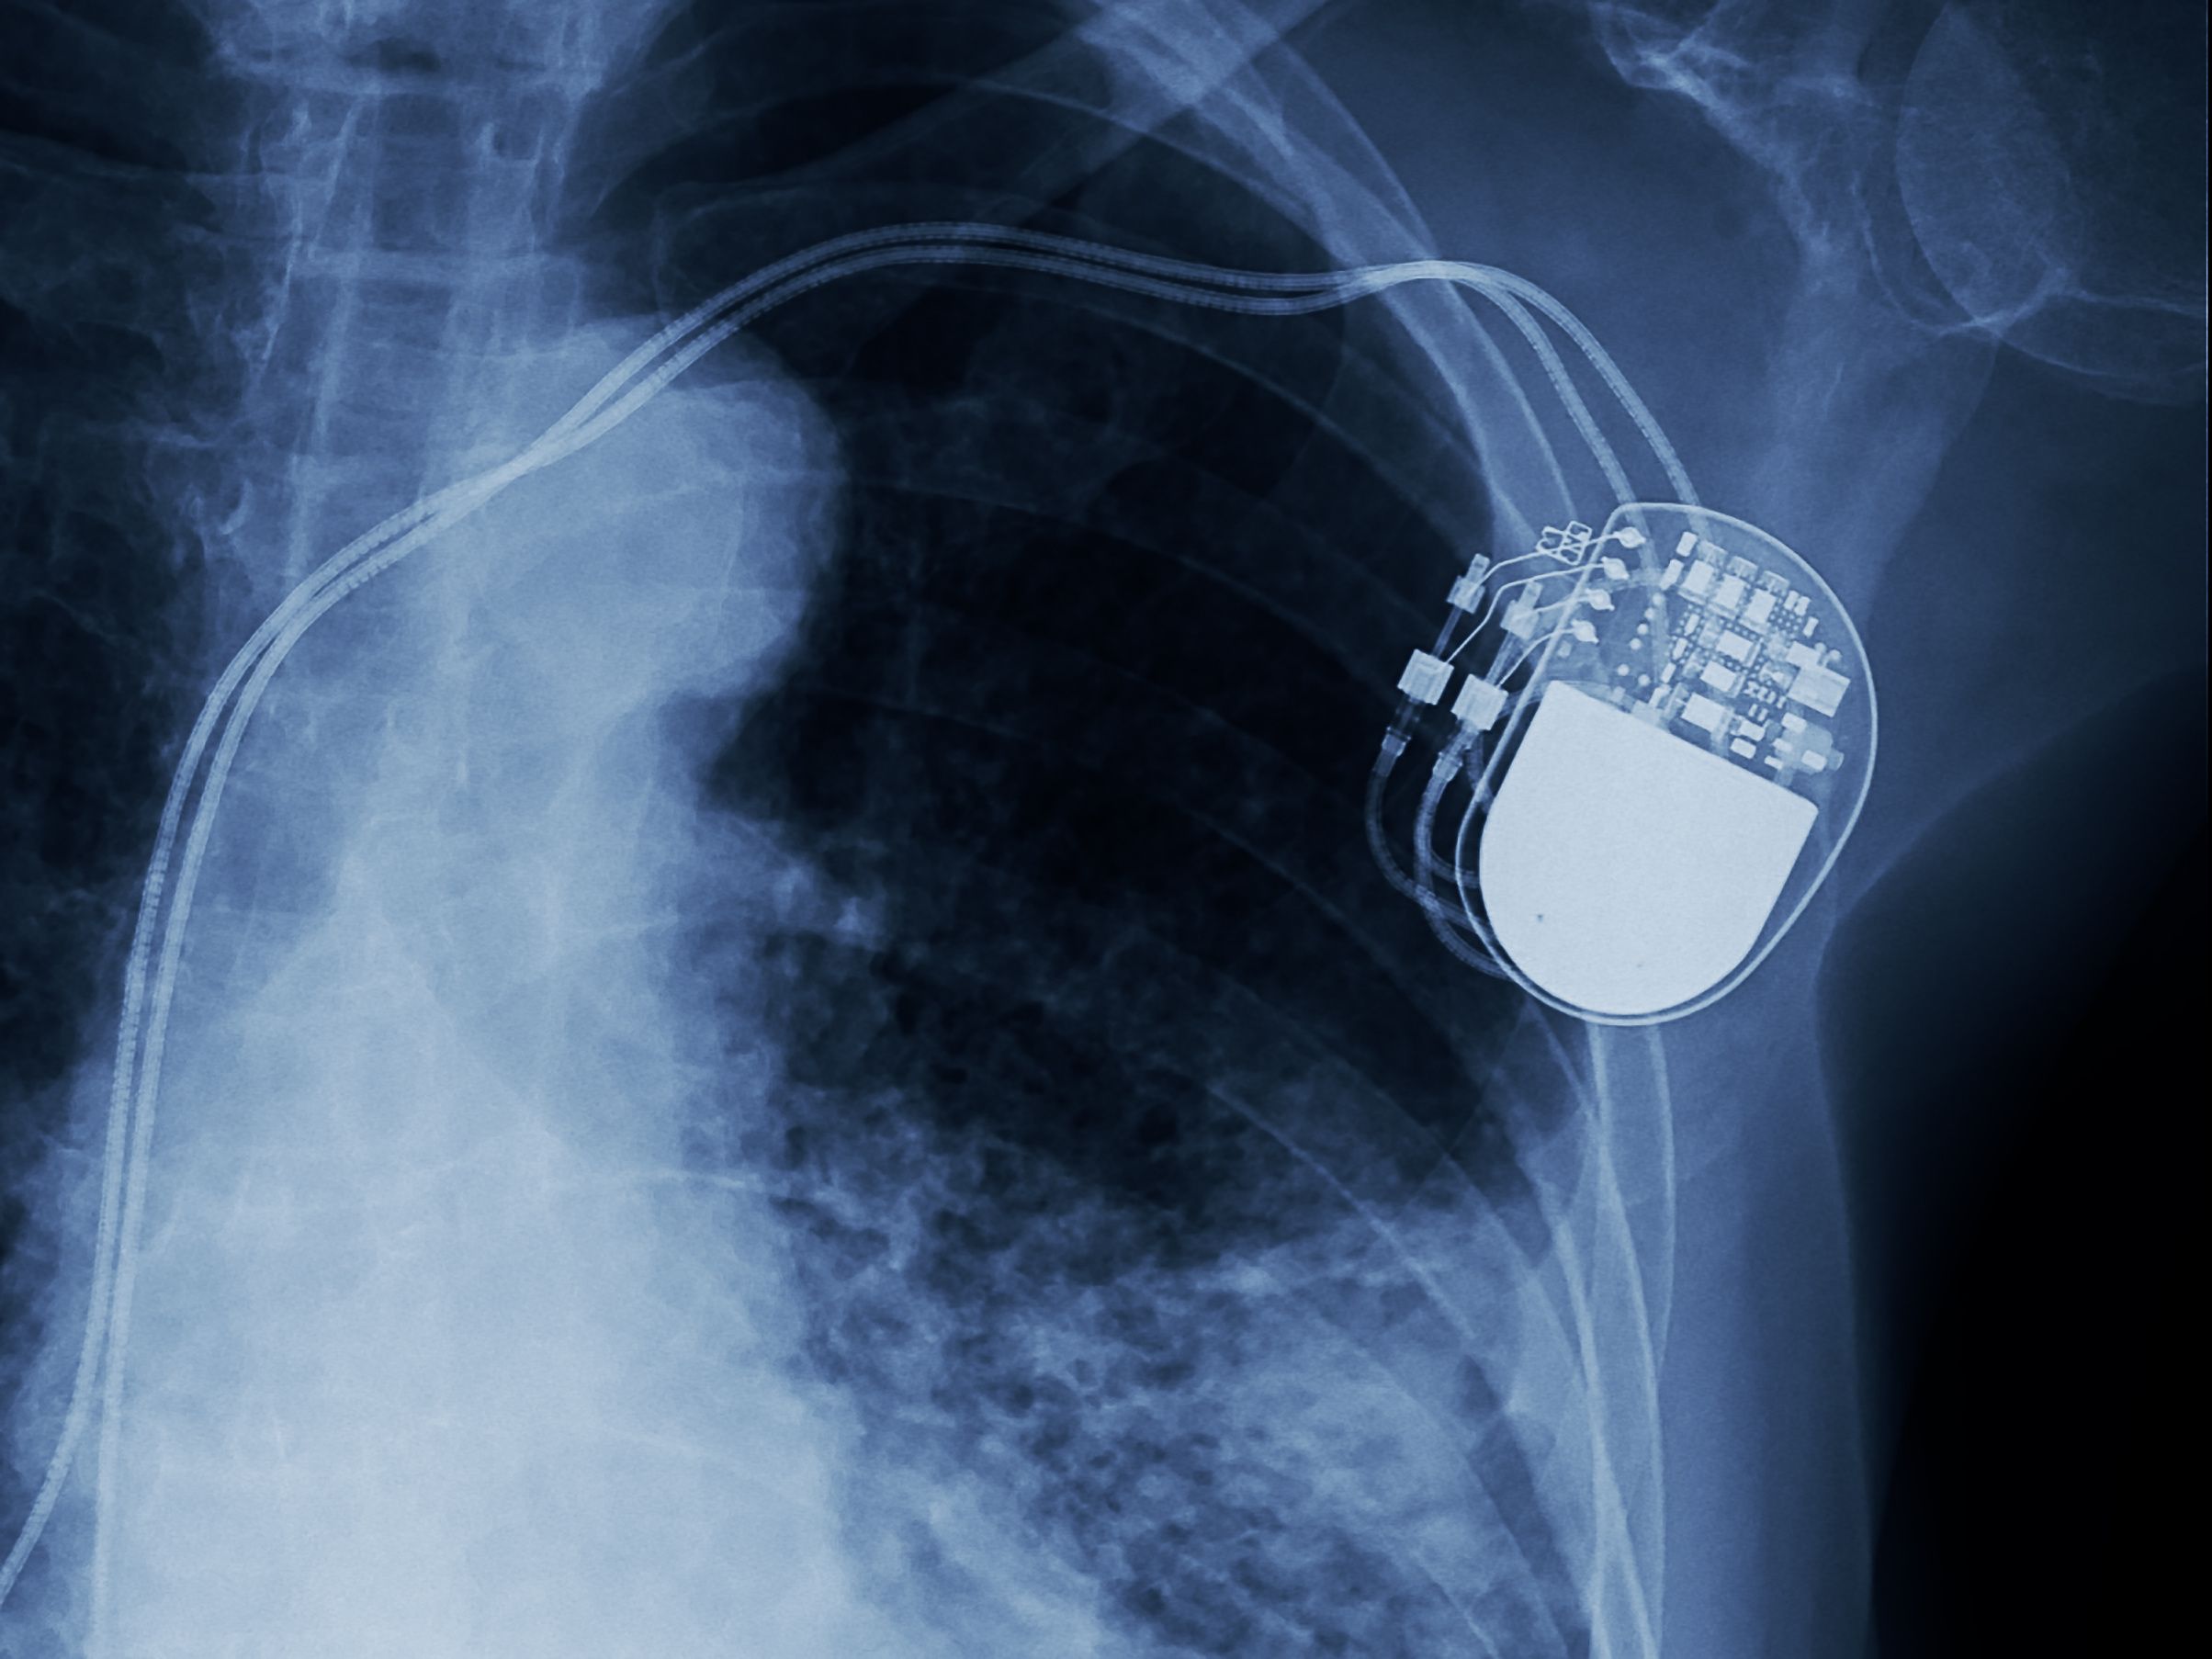

X-ray image of pacemaker | Image Credit: © Choo - © Choo - stock.adobe.com.